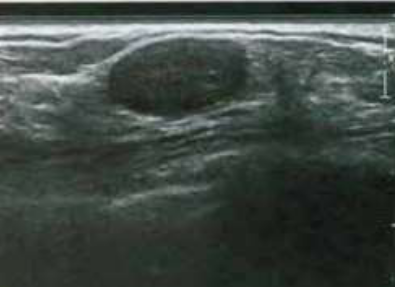

Paciente do sexo feminino, casada, nulípara, 42 anos, foi encaminhada para

avaliação ultrassonográfica das mamas, devido mamografia com classificação Birads 0. Ao exame observamos um nódulo oval, hipoecóico, sólido, paralelo à pele, contornos definidos, ausência de atenuação posterior, não se observa calcificações e o Doppler é negativo. Qual o possível diagnóstico?